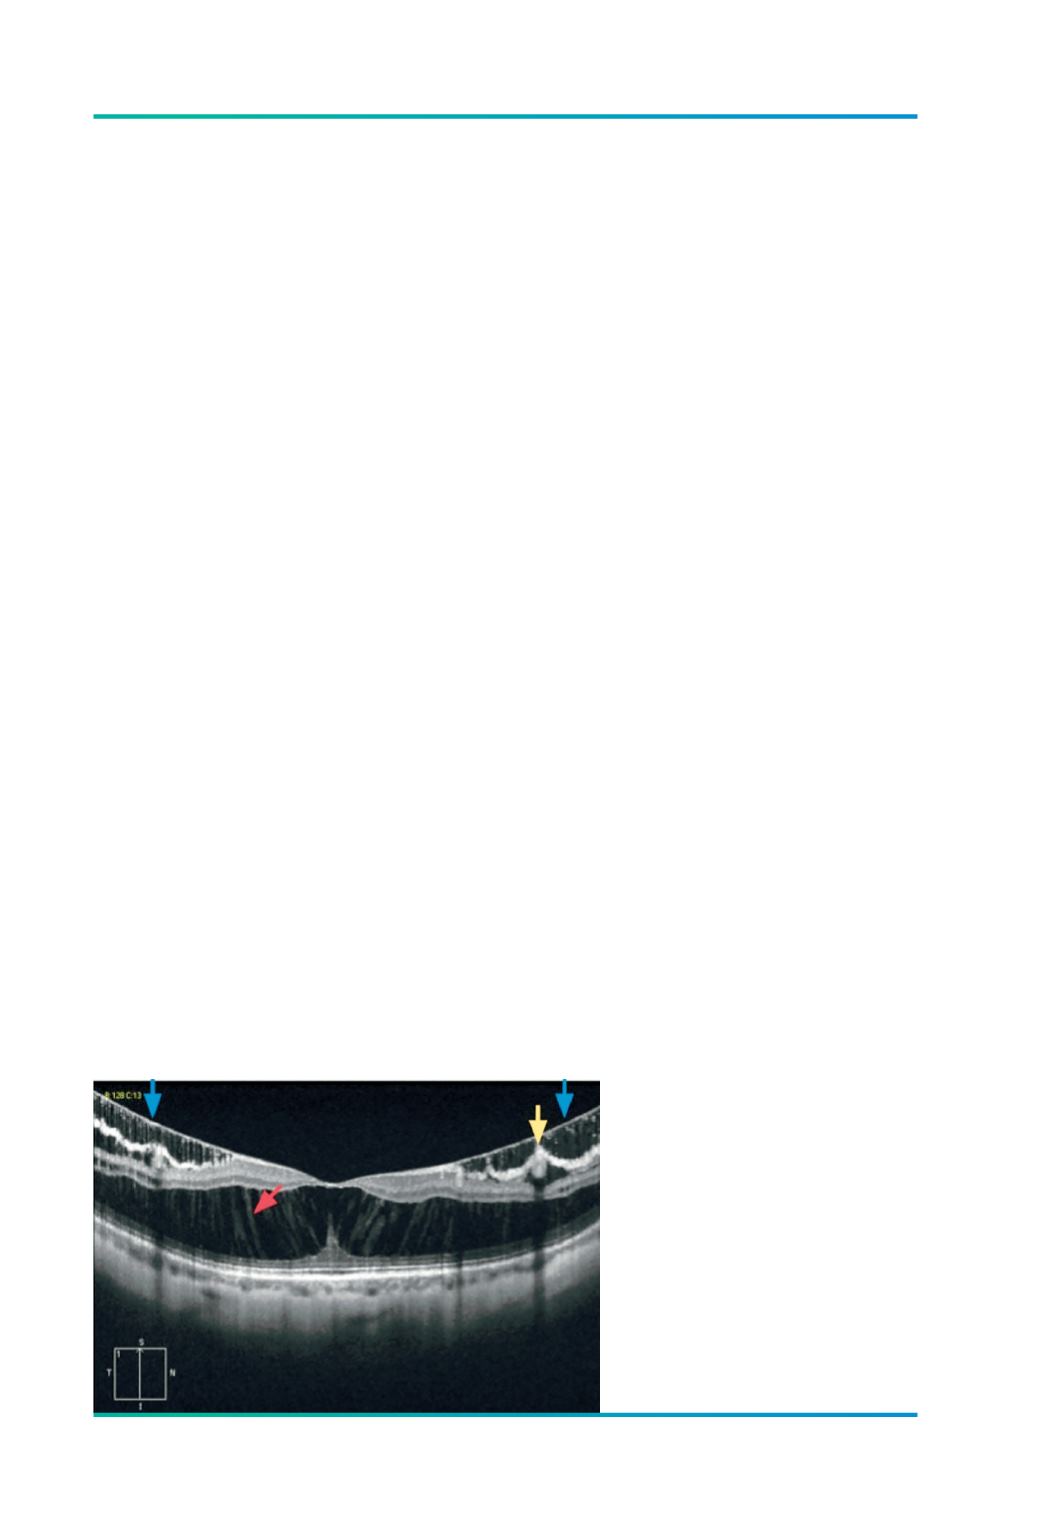

Figura 1.

Espessamento da retina em forma

de esquisis; “pontes” (

→

) que unem

as camadas internas e externas da

retina; descolamento da MLI (

);

micro pregas (

) retinianas em tenda.